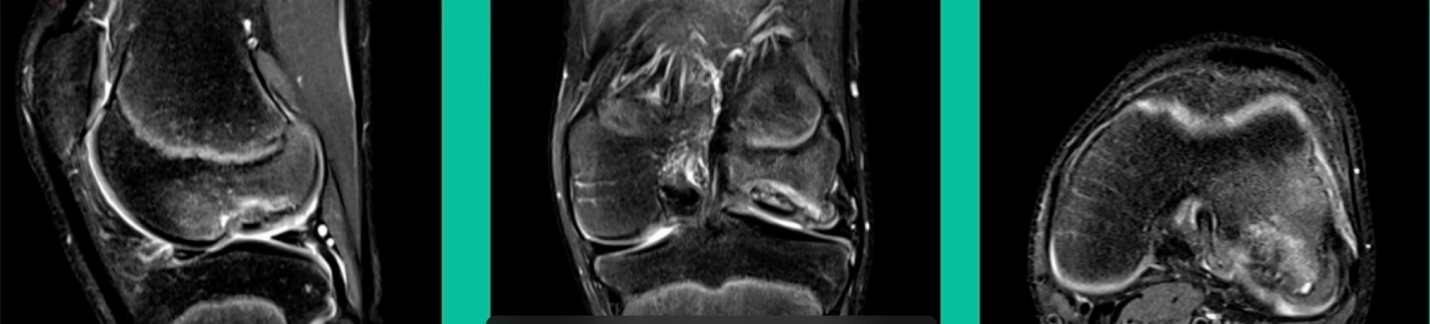

43-Year-Old, symptomatic medial femoral condyle.

D1 football player formally, affecting ADLs. For this one, I initially just wanted to watch it. This looks pretty small when he came in. Let’s see what happens. Six months later, this is where he progressed to.

We get in there, it’s delaminated, not much bone, nothing to fix in my mind, and so we drilled it.

How do these do? There’s actually reasonable data for marrow stimulation for OCD. But if you have the option for small defects, I would prefer an osteochondral allograft over microfracture based on the literature. That’s the take-home. Marrow stimulation, if you do it, you’re probably better off drilling it. We showed that we could reduce revision rates with marrow stimulation by two-thirds if you drill it versus use a microfracture awl.

Another one. 24-year-old right knee pain, ADL discomfort, normal alignment, lots of symptoms, thought I might be able to fix it.

I get in there, the pieces are just fragmented, I’m not going to fix it. This is the lateral aspect medial femoral condyle. Statistically, this one can do well. You take the piece out, they say, “I feel better.” It’s on the upslope of the lateral aspect medial femoral condyle. They feel fine, right? That’s not the case here. This one still continued to have symptoms.

So, what do we do for this one? This one got an osteochondral allograft.

I gave you a whole talk earlier on today about OA grafts. This is my mainstay for a salvage. I do not pull this out of the bag when the patient walks in the office for their first-line treatment. First, they get a scope. If it can’t be fixed, it comes out. If it can be fixed, we fix it with metal screws if it’s grossly unstable. If it’s not grossly unstable, we use biocomposite screws. If they get fixed, they go back to sports in four months. If they fail, they generally get this (Figure 28).

The results of osteochondral allograft in juveniles and adults, that’s the left and the right here, have been uniformly good. In juveniles, we get up to 90% success rates. Same thing for our adult onsets, a little bit less favorable. Even athletes can return to sport after an osteochondral allograft. Now we have 36 professional athletes that have had an osteochondral allograft who have gone back to sports. Some of them have had a meniscal allograft. So, salvage situation, you never make a promise, but it can’t happen.